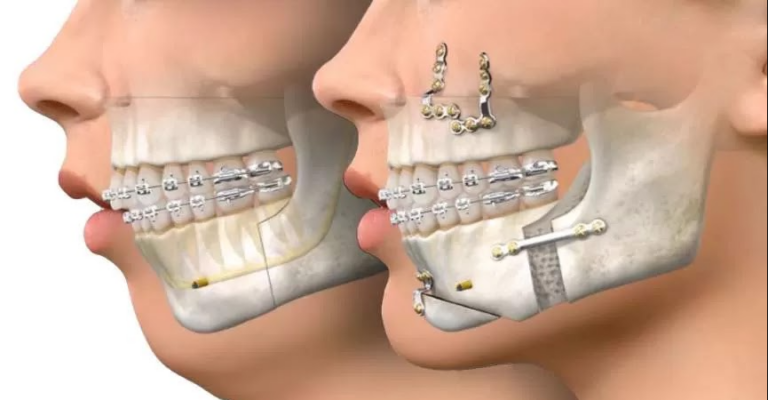

A cirurgia ortognática está indicada para pacientes com desarmonias esqueléticas e dentárias, cuja solução não pode ser propiciada apenas pelo tratamento ortodôntico – pois há um excesso ou falta de crescimento das bases ósseas da face. A cirurgia é indicada para pacientes com retrognatismo ou prognatismo mandibular, que consistem, respectivamente, na retrusão ou protrusão da mandíbula. Outros pacientes podem apresentar também problemas de crescimento na maxila ou até associados na maxila e mandíbula.

O tratamento convencional desse tipo de situação implica um tratamento ortodôntico prévio a uma cirurgia ortognática. A duração do tratamento ortodôntico prévio à cirurgia é de cerca de 1 ano e meio, e durante esse período os dentes têm sua posição corrigida para viabilizar a realização da cirurgia ortognática. Após o procedimento cirúrgico, o tratamento ortodôntico continua por um período que varia de caso para caso.

Essa nova abordagem tornou-se possível devido à incorporação de novas tecnologias disponíveis para o tratamento ortodôntico. A cirurgia continua a ser feita por um cirurgião buco maxilofacial e existem poucas diferenças em relação à operação tradicional. Ao início do tratamento, o aparelho ortodôntico é instalado e a cirurgia é realizada – sem a ortodontia prévia que piora a estética do paciente. O objetivo da cirurgia é corrigir as bases ósseas, melhorar a estética facial e instalar implantes temporários – mini placas – para permitir que o ortodontista corrija as posições dentárias no pós-cirúrgico. Após a cirurgia, o paciente continua o tratamento ortodôntico para correção da má oclusão.